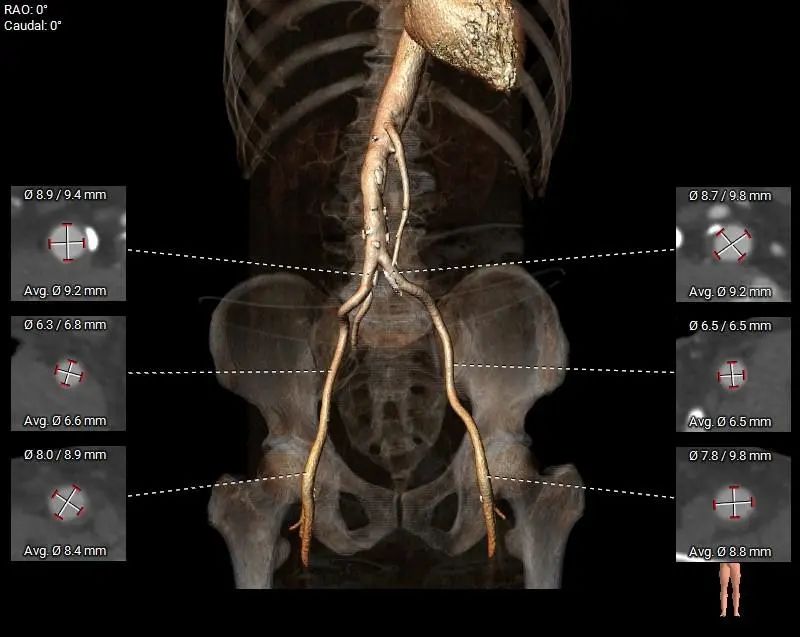

术中体位

外周入路

外周入路尚可